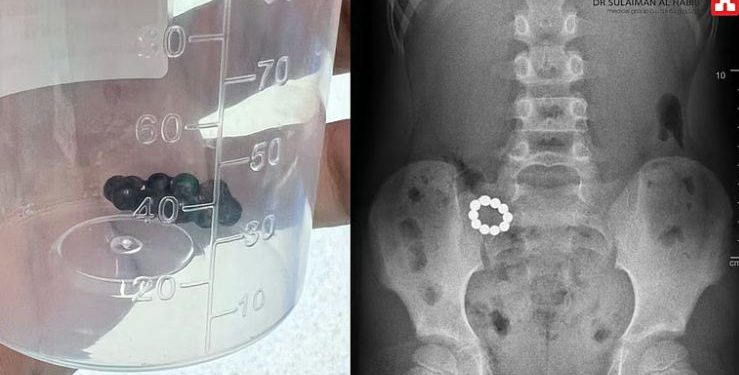

تمكن فريق طبي متخصص في مستشفى الدكتور سليمان الحبيب بالصحافة من إنقاذ حياة طفل يبلغ من العمر 8 سنوات، ابتلع 10 كرات مغناطيسية دائرية أثناء اللعب بها، مما تسبب له في تلف شديد في جدار المعدة والقولون.

أوضح د. عبدالدائم أنه فور وصول الطفل إلى المستشفى، تم إجراء عدة فحوصات دقيقة، بما في ذلك أشعة سينية (X-ray) و تصوير مقطعي محوسب (CT-scan)، حيث أظهرت الفحوصات أن الطفل قد ابتلع 10 كرات مغناطيسية، وتسببت خاصية التجاذب والتنافر بين الكرات في حدوث تلف وثقوب في جدار المعدة والقولون.

وأشار إلى أن الكرات المغناطيسية تفاعلت بشكل خطير داخل الجهاز الهضمي للطفل، ما أدى إلى انسداد الأمعاء وتمزق الأنسجة الداخلية. وفي ضوء هذه النتائج، قرر الفريق الطبي اتخاذ إجراءات علاجية فورية.

عملية جراحية ناجحة

قام الفريق الطبي بإجراء عملية عاجلة باستخدام المنظار الجراحي لإزالة الكرات المغناطيسية، حيث تم معالجة الثقوب الناتجة عن التجاذب المغناطيسي، وكذلك استئصال الأجزاء التالفة من الأمعاء الدقيقة، ثم إعادة توصيل الأجزاء السليمة عبر فتحة جراحية صغيرة. استمرت العملية لمدة 4 ساعات، وانتهت بنجاح تام ودون أي مضاعفات.